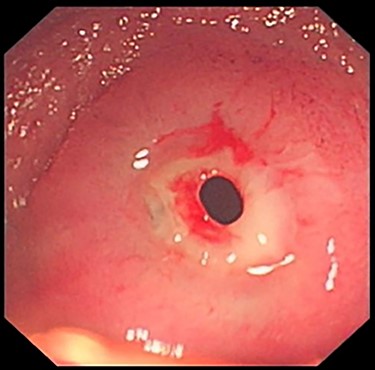

Initial investigations included magnetic resonance enterography that was normal and a capsule endoscopy that showed rare erosions, aphthoid ulcers and two ulcerated stenosis (Fig. 1).

No other particular anomalies were perceived and a small enterotomy was performed 35 cm above the Bauhin valve near the previous stricturoplasty. The peroperative enteroscopy reached proximally the duodeno-jejunal angle and distally the ileocaecal valve and the caecum allowing the exploration of the entire small bowel (Fig. 4). It showed multiple ileal diaphragm including three diaphragms with small ulcers (video). A 60 cm segmental resection was performed removing all the six lesions and the histological features found in the lesion were consistent with the diaphragm disease.